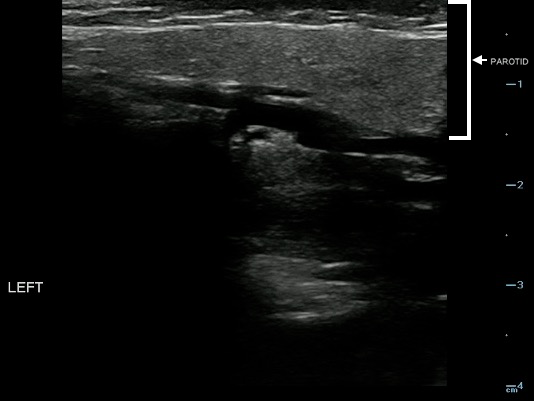

- Figure 18. Normal parotid gland (marked with arrow)

Video 12. Normal parotid gland

- Sonographically, the normal parotid and submandibular glands appear homogeneous; the fatty glandular tissue composition causes an increased echogenicity relative to adjacent muscle.

- Parotid Gland:

- The homogeneity and echogenicity of the parotid gland is comparable to that of the thyroid gland.

- Normal intraglandular salivary ducts and the Stensen’s duct are generally not visualized with ultrasound.

- When dilated, Stensen’s duct is visualized superficially along the masseter muscle, typically 1 cm below the zygomatic arch.

- Parotid short axis should be less than 5– 6 mm normally.13

- Normal variants:

- The Parotid gland has intraglandular lymph nodes that are commonly seen within the parenchyma of the parotid gland.

- Figure 19 and 20. Parotid gland lymph nodes

Video 14. Parotid gland lymph nodes